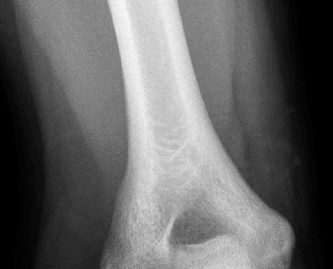

CASE 40 A 16-year-old male baseball player presents to your office for evaluati…